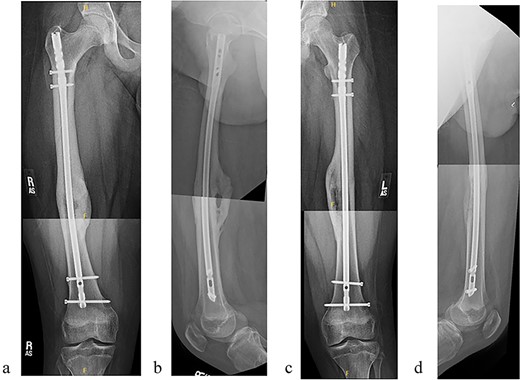

The patient tolerated the procedure well and recovered uneventfully. He was noted to have circumferential osseous healing at 1 year and underwent bilateral femur IMN removal 1.5 years postoperative without complication (Figs 4a–d and 5a–d).

(a) Right femur AP radiograph. (b) Right femur lateral radiograph. (c) Left femur AP radiograph. (d) Left femur lateral radiograph.